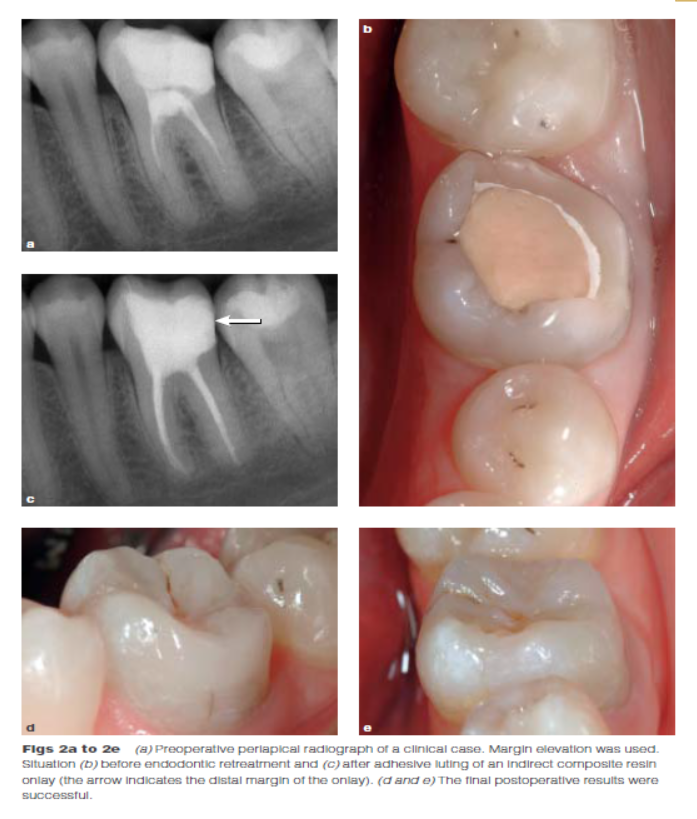

DME是用一個改良彎曲的成型片接堆放復(fù)合樹脂來提升齦壁高度,使其能夠在修復(fù)過程中使用橡皮障封閉邊緣,可以在固化前適當(dāng)?shù)囊瞥嘤嗟膹?fù)合樹脂。DME應(yīng)該在即刻牙本質(zhì)封閉(IDS)之后,在使用橡皮障的條件下,且僅在邊緣可被改良的成型片適當(dāng)隔離時直接獲得。否則,這個技術(shù)不能使用。在最終取印前,需要拍攝咬合翼片來評估復(fù)合樹脂在齦邊緣區(qū)域的密合度(有無懸突或缺陷)。同樣需要仔細(xì)隨訪來評估軟組織的健康和是否需要外科手術(shù)干預(yù)。只要可能,在牙髓治療前就應(yīng)通過DME術(shù)制造假壁,使根管治療更完善(圖2、3)。圖4展示了一個典型DME術(shù)的適應(yīng)癥。

Dietschi和Spreafico在1998年提出了另一種方法,即在間接修復(fù)體的下面放置一個復(fù)合樹脂基底來取代冠向提升邊緣(圖1)。這個方法即我們所知的齦壁提升術(shù)(DMG)是在橡皮障隔離下完成的?(This procedure,…,is performed under rubber dam isolation following the placement of a matrix.)如今,DME(齦壁提升術(shù))通常與IDS(即刻牙本質(zhì)封閉術(shù))聯(lián)合使用來促進(jìn)間接粘接修復(fù)體的粘接和齦邊緣的封閉。此外,邊緣的齦上提升,粘接復(fù)合樹脂基底被用于封閉牙本質(zhì)、加強(qiáng)潛在牙尖?(reinforce undermined cusps),充填倒凹(fill undercuts),以及為嵌體/高嵌體修復(fù)提供必要的幾何形態(tài)。